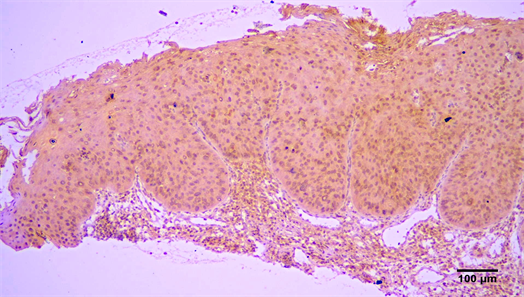

(Figure 3), but this correlation was not statistically significant (Table 2). Finally, Arp2 and Arp3 expression was more common in well differentiated OSCC compared to moderate or poorly differentiated OSCC, but statistical significance between grade and expression was not seen (Table 4).

Figure 3. Immunohistochemical expression of Arp3 (+++) in a in situ carcinoma (streptavidin-biotin-peroxidase immunostaining, original magnification ×10).

Arp2 and Arp3 are more commonly expressed in invasive than in intramucosal carcinomas of the colon, as well as in gastric carcinomas than in intestinal metaplasia and gastritis [12] [13]. In various tumors Arp2/3 expression ispositively correlated to tumor size, depth of invasion, venous invasion and higher stage disease [13] [14] [15] [16] [17]. In colorectal adenocarcinomas Arp2/3 expression was higher in cases with liver metastasis and in moderately differentiated tumors [15] while ingliomas increased Arp2/3 expression was associated with higher stage disease and Arp2/3 upregulation was seen in migrating cells [17]. The immunohistochemical expression of ARPC2 was included in a multimarker diagnostic assay that was able to correctly distinguish melanomas from benign and atypical nevi [26]. Co-expression of Arp2 and Wave2, a member of the WASP protein family binding to Arp2/3 complex to form lamellipodial protrusions, was an independent risk factor for colorectal carcinoma with liver metastasis [15]. It was, also, detected more frequently in cases of lung carcinoma with lymph node metastasis and poor outcome [16] , and was significantly different between invasive and not invasive carcinoma of the breast, and poor clinical outcome [14]. In the present study, Arp2/3 was more commonly expressed in invasive OSCC than in non-invasive verrucous carcinoma and carcinoma in situ, although this correlation was not found to be statistically significant, possibly due to small number of non-invasive cases included. The difference found in Arp3 expression between invasive OSCCs and verrucous carcinoma should be further examined, as it could be utilized in recognizing invasive cells in verrucous carcinoma.